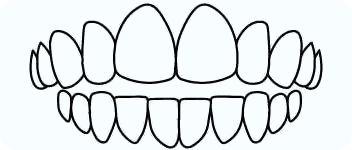

Over Bite

An over bite is when the upper front teeth close down too deeply over the lower front teeth.